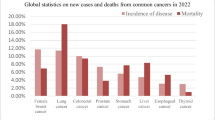

Sung H, Ferlay J, Siegel RL et al (2021) Global Cancer Statistics 2020: GLOBOCAN estimates of incidence and mortality worldwide for 36 cancers in 185 countries. CA: Cancer J Clin 71:209–249. https://doi.org/10.3322/caac.21660